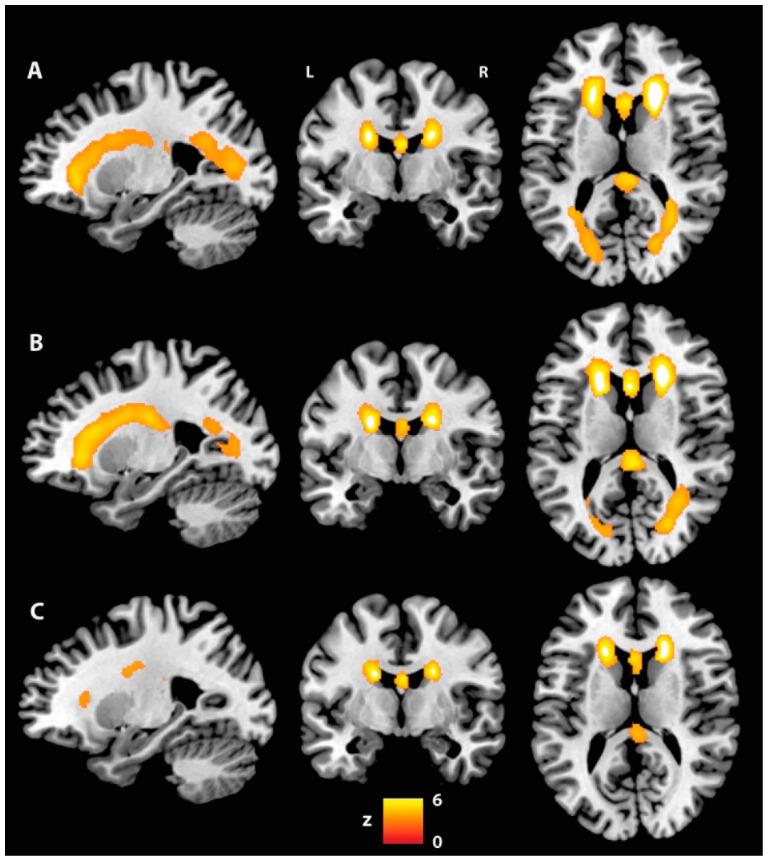

Apathy is the commonest neuropsychiatric symptom in Alzheimer's disease (AD). Previous findings suggest that apathy is caused by a communication breakdown between functional neural networks involved in motivational-affective processing. This study investigated the relationship between white matter (WM) damage and apathy in AD. Sixty-one patients with apathy (AP-PT) and 61 without apathy (NA-PT) were identified from the Alzheimer's Disease Neuroimaging Initiative (ADNI) database and matched for cognitive status, age and education. Sixty-one cognitively unimpaired (CU) participants were also included as controls. Data on cognitive performance, cerebrospinal fluid biomarkers, brain/WM hyperintensity volumes and diffusion tensor imaging indices were compared across groups. No neurocognitive differences were found between patient groups, but the AP-PT group had more severe neuropsychiatric symptoms. Compared with CU participants, only apathetic patients had deficits on the Clock Drawing Test. AP-PT had increased WM damage, both macrostructurally, i.e., larger WM hyperintensity volume, and microstructurally, i.e., increased radial/axial diffusivity and reduced fractional anisotropy in the fornix, cingulum, anterior thalamic radiations and superior longitudinal and uncinate fasciculi. AP-PT showed signs of extensive WM damage, especially in associative tracts in the frontal lobes, fornix and cingulum. Disruption in structural connectivity might affect crucial functional inter-network communication, resulting in motivational deficits and worse cognitive decline.

冷漠是阿尔茨海默病(AD)最常见的神经精神症状。先前的研究结果表明,冷漠是由参与动机-情感加工的功能性神经网络之间的沟通障碍所致。本研究调查了AD患者白质(WM)损伤与冷漠之间的关系。从阿尔茨海默病神经影像倡议(ADNI)数据库中识别出61名有冷漠症状的患者(AP-PT)和61名无冷漠症状的患者(NA-PT),并根据认知状态、年龄和教育程度进行匹配。还纳入了61名认知未受损(CU)的参与者作为对照。对各组的认知表现、脑脊液生物标志物、脑/WM高强度体积和扩散张量成像指标数据进行了比较。患者组之间未发现神经认知差异,但AP-PT组有更严重的神经精神症状。与CU参与者相比,只有冷漠患者在画钟试验中有缺陷。AP-PT在宏观结构上(即更大的WM高强度体积)和微观结构上(即穹窿、扣带、丘脑前辐射以及上纵束和钩束的径向/轴向扩散率增加和分数各向异性降低)都有更严重的WM损伤。AP-PT表现出广泛WM损伤的迹象,尤其是额叶联想束、穹窿和扣带中的损伤。结构连接性的破坏可能会影响关键的功能网络间通信,导致动机缺陷和更严重的认知衰退。